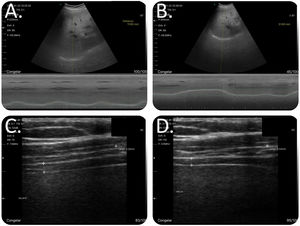

To measure diaphragmatic mobility, the patients were placed in supine decubitus, with the bed angled at 30–45°. We used the convex probe in B-mode to examine the right diaphragm, with the ultrasonic beam in the cephalic-dorsal direction, with the ultrasound probe below the costal arch in the midclavicular line. Once the diaphragm had been located, the ultrasound was changed to M-mode, and the patients were given indications so as to perform measurements at tidal volume and during maximum inspiration and expiration (Videos 1 and 2).

To measure the diaphragm thickness, the patients were placed in the seated position, with the shoulders at 90° and the linear probe in B-mode. In this measurement, the ultrasonic beam was aimed in the craniocaudal direction, perpendicular to the direction of the muscle fibers, including the pleural and peritoneal membrane (Fig. 2). Patients were asked to breathe at tidal volume; once the zone of apposition had been located, they were requested to breathe at tidal volume (Video 3), perform a forced inspiration until total lung capacity had been achieved (Video 4) and then perform a forced expiration (Video 5). All images were collected in jpeg format and on video. To diagnose the diaphragmatic dysfunction (DD), we used the TfDi in forced maneuvers, with a cutoff<20% according to literature reviewed.15

Methodology for examining the diaphragm. To measure diaphragmatic mobility, the patients were placed in supine decubitus, with the bed angled at 30–45°, with the ultrasound probe below the costal arch in the midclavicular line and with the ultrasonic beam in the cephalic-dorsal direction, pointing toward the right shoulder. The diaphragm thickness was measured with the patient seated and the shoulder at 90°. The ultrasonic beam was aimed in the craniocaudal direction, perpendicular to the direction of the muscle fibers, including the pleural and peritoneal membrane. (A) Combined B/M-mode study with convex probe during a maneuver at tidal volume. In M-mode, we observed the sinusoidal image that represented the diaphragm's movement at tidal volume. (B) Combined B/M-mode study with convex probe during a forced maneuver. In M-mode, the wave is no longer sinusoidal; however, there is a large amplitude in its movement. The highest part of the line corresponds to the deep inspiration and the lowest part corresponds to the maximum expiration. (C) B-mode study with linear catheter during a forced inspiration maneuver. We can see the diaphragm's typical morphology as a structure with 2 parallel hyperechogenic lines and a third line between the two lines, with lower intensity hyperechogenicity that is not always visible. At the end of the inspiration, the diaphragm reaches its maximum thickening. (D) B-mode study with linear catheter during a forced expiration maneuver. At the end of the forced expiration, the diaphragm reaches its maximum narrowing.